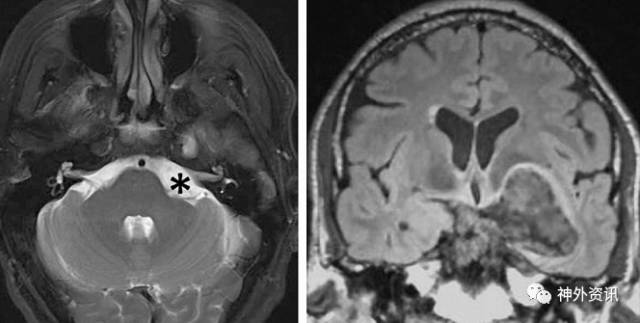

在临床中可经常发现由于注射肉毒素或持续不断的痉挛导致的面肌无力以及周围血管性病变导致的面部肌肉萎缩。任何伴发的可疑症状如听力丧失都应该排除桥小脑角区的占位性病变如神经鞘瘤,脑膜瘤,胆脂瘤或蛛网膜囊肿。另外,一些脑干原发病变如胶质瘤,多发性硬化,脑干卒中也会引起相似的症状,也应予以鉴别。

图3. 此巨大左侧岩斜区胆脂瘤(注意桥小脑角区面神经周围区域扩大)仅表现为同侧面肌痉挛。此病例通过乙状窦后入路和翼点入路分期切除。